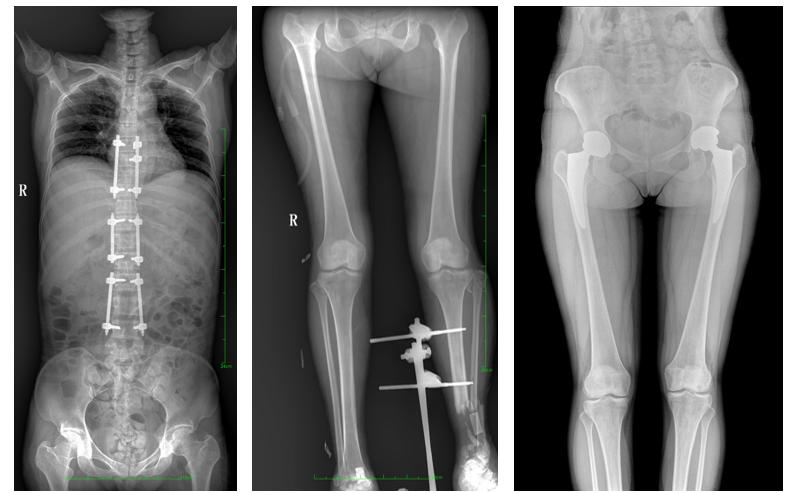

全脊柱一次成像 不拼接

17"*34"有效視野,是市面大尺寸平板的2倍,一次成像不拼接。相較于多張攝影再軟件拼接的DR設(shè)備,PLX8600解決了拼接圖像存在密度不均勻,拼接處圖像配準(zhǔn)和放大效應(yīng)等問(wèn)題,給臨床帶來(lái)了真正的大視野影像解決方案,高清畫(huà)質(zhì),準(zhǔn)確成像不失真,可一次性覆蓋全脊柱或雙下肢影像。PLX8600大視野平板動(dòng)態(tài)DR攝影速度快,患者可以更快的完成檢查,且單次攝影輻射劑量是常規(guī)多張攝影再軟件拼接DR的1/2或1/3,低劑量給患者更多關(guān)愛(ài)。